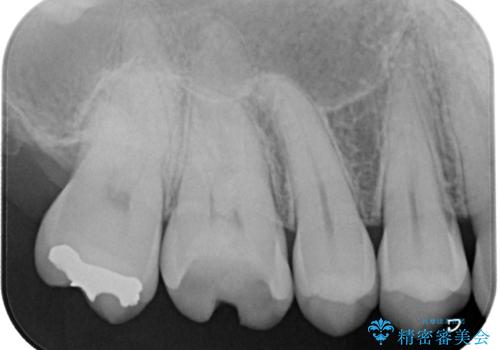

- 以前他院で治療した銀歯が外れてしまったとのことで来院された患者様です。

精査の結果、歯の神経は問題ないですが、欠損している範囲が大きいため部分的な詰め物では脱離や破折のリスクが高いため、オールセラミッククラウンによる補綴治療を行っていくこととしました。